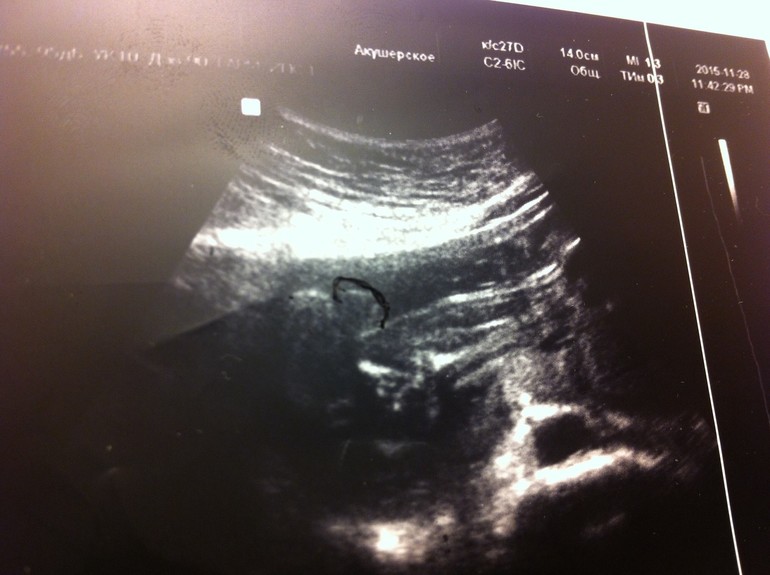

Может, кто по фото может все-таки что-то сказать? Первое фото - 24 неделя, где увидели девочку. 2 и 3 фото - 25 неделя, где увидели мальчика (врач маркером яички обвела). Пениса не видно, говорит, что это яички такие большие, половые губы такими не бывают... И тогда, и тогда говорят "100%". Ну смешно уже...

Тут сказали мальчик: